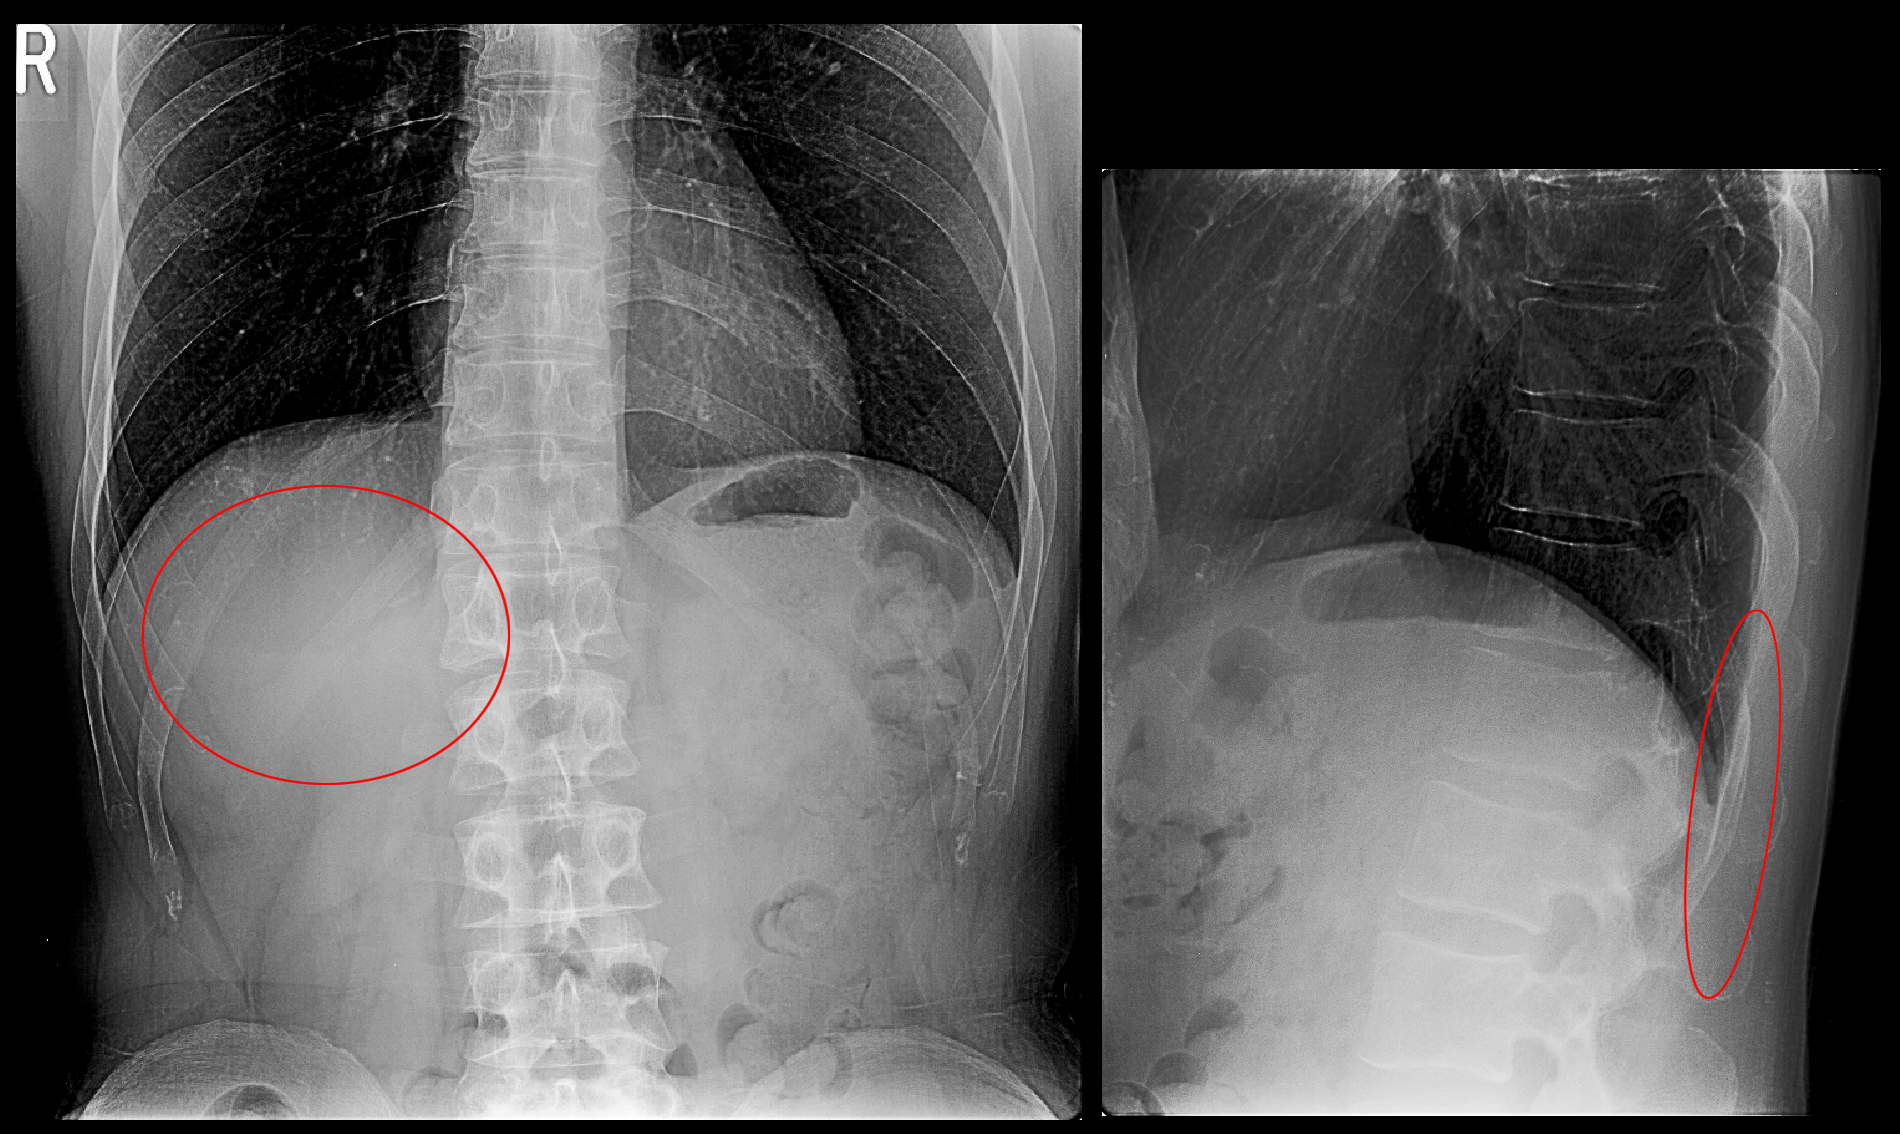

54才の男性です。事務職の方ですが、平成23年9月18日に会社のイベントでテント固定用の錘を持って腰がピリッといって腰痛が発症し、同日夜に寝た時に腰痛が悪化し、ほとんど眠れなかったということで、9月19日に当院を受診されました。

赤丸部分が痛みの部位となりますが、通常の腰痛に比して背中よりであることから腰痛の原因を確認するためにMRI検査を勧めたところ、患者さんに同意していただけました。

MRI検査所見では椎間板の変性と脊髄の刺激はみられず、T2矢状断でもT1矢状断でもL1椎体の上縁の中央部が黒くなっており、骨の輪郭(皮質)が軽度陥凹しています。これは錘を持った荷重負荷でL1(第1腰椎)が壊れたことにより発症した腰痛であると診断されます。鎮痛薬の処方とともに骨を丈夫にするための骨粗鬆症薬の処方も開始しました。しかし、それ以上に重要なことは安静です。安静といっても自宅で寝ていなければならないというようなことではなく、重い物は持たない、中腰、前屈の作業はしない、階段の昇降の機会をできる限り減らす、必要以上に動き回らないというような意識をもつこととなります。

10月3日の2週後の再診時のレントゲン像では、損傷したL1の上下の椎体はその高さは同じですが、L1の椎体は31㎜から29㎜に2㎜潰れが進行しています。初診時L1の椎体損傷が診断されていて、安静を意識して生活していたはずです。レントゲンだけの診療で「異常はありません」と診断されてシップ等の処方で生活していれば、多少痛くても腰痛を我慢して通常の生活を続けることになり、L1椎体の潰れはもっと大きくなっていたはずと推察します。患者さんには5週間安静を心がけてもらい、腰痛は落ち着きました。